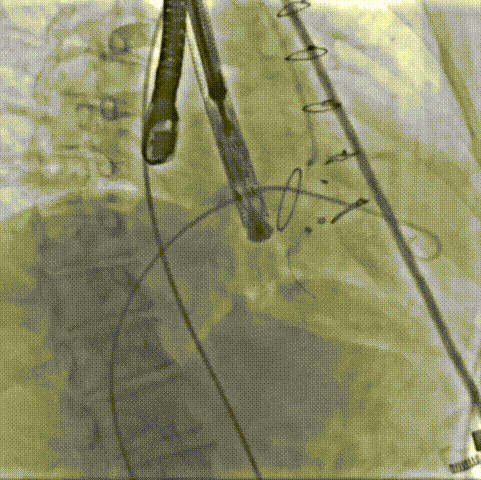

手术在患者全麻状态下进行,采用经右侧颈静脉作为入路,将装载有人工瓣膜的输送器缓慢推送至右心房;并在经食道超声和DSA的引导下小心调整输送器角度,将输送器送入右心室;逐步释放瓣膜锚定装置和盘片,调整瓣膜位置后,锚定瓣膜完成植入。术后右房压明显下降,从术前的25/10(16) mmHg降至术后即刻的12/7(10) mmHg,术后超声提示人工三尖瓣同轴性良好,固定牢固,无反流及瓣周漏手术室即刻拔除气管插管。

术中造影